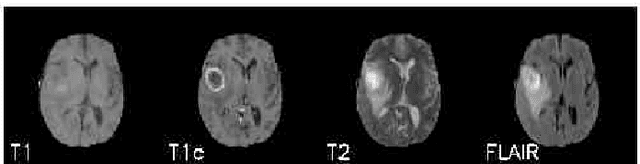

Abstract:The analysis of Magnetic Resonance Imaging (MRI) sequences enables clinical professionals to monitor the progression of a brain tumor. As the interest for automatizing brain volume MRI analysis increases, it becomes convenient to have each sequence well identified. However, the unstandardized naming of MRI sequences makes their identification difficult for automated systems, as well as makes it difficult for researches to generate or use datasets for machine learning research. In the face of that, we propose a system for identifying types of brain MRI sequences based on deep learning. By training a Convolutional Neural Network (CNN) based on 18-layer ResNet architecture, our system can classify a volumetric brain MRI as a FLAIR, T1, T1c or T2 sequence, or whether it does not belong to any of these classes. The network was evaluated on publicly available datasets comprising both, pre-processed (BraTS dataset) and non-pre-processed (TCGA-GBM dataset), image types with diverse acquisition protocols, requiring only a few slices of the volume for training. Our system can classify among sequence types with an accuracy of 96.81%.